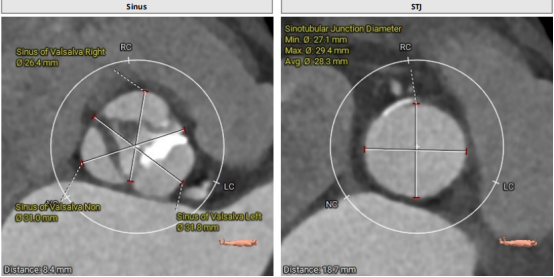

CT結(jié)構(gòu)評估

患者為功能性二葉瓣,瓣葉增厚,輕度鈣化,鈣化主要集中在左竇瓣葉上,左冠脈高度較低,結(jié)合瓣葉長度,竇部結(jié)構(gòu)綜合評估左冠風(fēng)險較低,但左冠瓣葉瓣尖處有鈣化團塊,在球擴以及瓣膜釋放時仍需注意左冠灌注情況,由于鈣化團塊位置特殊,建議做冠脈保護處理,右側(cè)股動脈作為主入路,穿刺點位于股骨頭中段即可。